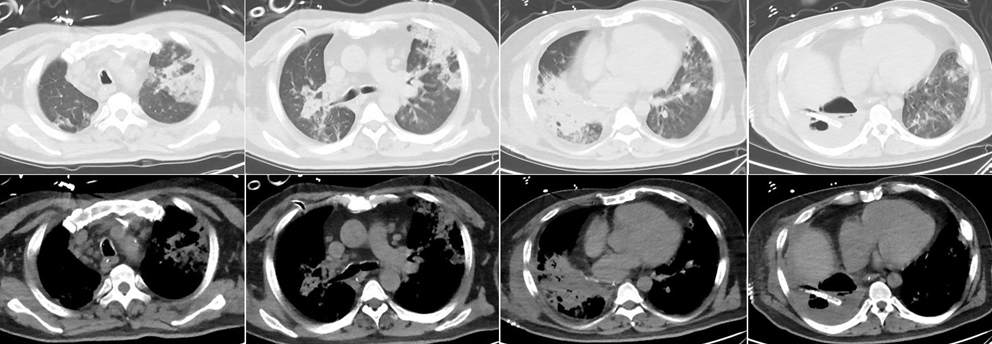

• 4月4日出现喘憋,并逐渐加重,夜间无法平卧。

• 4月5日于我院急诊就诊,测体温38.5℃。动脉血气分析(FiO2 0.29):pH 7.473,PaO2 57.2 mmHg,PaCO2 34.6 mmHg。急诊化验:WBC 14.99×109/L,NEU% 91.8%,LYM 0.61×109/L,血钠127 mmol/L,D-二聚体7470 ng/ml,C反应蛋白(CRP)350.7 mg/L,白介素-6(IL-6) 283.1 pg/ml,降钙素原(PCT)<0.5 ng/ml。胸部CT:右肺多发感染、实变,空洞影伴液平形成,伴右侧少量胸腔积液、部分包裹,左肺下舌段炎性灶(图1)。胸腔超声:右侧胸腔可见液性暗区,最深约6.0 cm,内可见大量分隔,部分区域呈蜂窝状。急诊以“重症肺炎(右侧)肺脓肿”收入我科。

图片

图1  患者胸部CT(2020年4月5日)